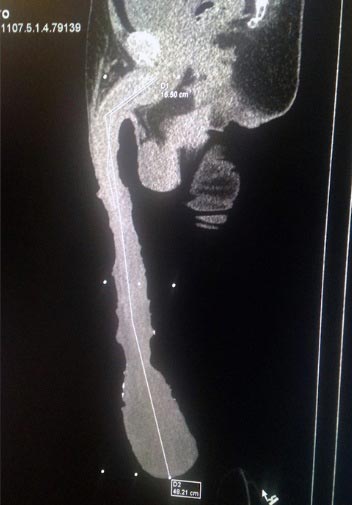

โรแบร์โตค้นพบว่าตัวเองมีน้องชายใหญ่โตกว่าคนปกติตั้งแต่ตอนที่ยังเป็นวัยรุ่น เขาหมกมุ่นอยู่กับมันมากและพยายามทุกทางให้มันใหญ่โตยิ่งขึ้นไปอีก เขาหาผ้ายืดมาพันมันเพื่อเพิ่มน้ำหนักและทำการยืดให้มันยาว ๆ ขึ้น จนจบที่ขนาด 18.9 นิ้วในทุกวันนี้

โรแบร์โต กล่าวว่า เขามีความสุขดีกับน้องชายขนาดมหึมาของเขา เขากล่าวว่าสิ่งนี้มันทำให้เขามีชื่อเสียงและทำให้โลกรู้จักเขา เขาอยากมีชื่อปรากฏบนหน้ากินเนสส์บุ๊ก ซึ่งดูเหมือนว่าตอนนี้กินเนสส์ยังไม่ได้ทำการจัดสถิติด้านนี้ ถึงแม้ว่าโรแบร์โตจะภาคภูมิใจกับความเป็นชายของเขามาก แต่เขาก็ได้รับคำแนะนำจากแพทย์ว่าควรผ่าตัดเพื่อทำการลดขนาดมันซะ

อวัยวะเพศที่ใหญ่ยาวทำให้โรแบร์โตประสบปัญหาด้านสุขภาพหลายอย่าง เขาต้องเอาผ้าพันอวัยวะเพศเอาไว้ตลอดเวลาเพื่อป้องกันการบอบช้ำหรือระคายเคืองจากการเสียดสี ตอนจะนอนก็ต้องเอาอวัยวะเพศวางไว้บนหมอน เขาต้องประสบภาวะติดเชื้อในทางเดินปัสสาวะอยู่บ่อยครั้ง เนื่องจากเวลาที่เขาขับถ่ายเบา ปัสสาวะไม่สามารถไหลออกมาได้หมดและคั่งค้างอยู่ในหนังหุ้มปลาย และขนาดของมันทำให้เขาไม่สามารถประกอบกิจกรรมทางเพศกับใครได้

นายแพทย์เฆซุส ดาบิด ซาลาซาร์ กอนซาเลซ แพทย์ผู้เชี่ยวชาญด้านสรีรวิทยาเพศชาย เคยให้คำแนะนำกับโรแบร์โตในด้านนี้ โดยกล่าวว่าโรแบร์โตควรได้รับการผ่าตัดเพื่อทำการรักษาอวัยวะเพศ เมื่อผ่าตัดแล้วเขาจะมีอวัยวะเพศที่ขนาดปกติเหมือนคนทั่วไป ไม่ต้องเจอปัญหาสุขภาพ และสามารถมีเพศสัมพันธ์ได้โดยไม่เจ็บปวด อีกทั้งยังสามารถมีลูกได้อีกด้วย แต่โรแบร์โตยืนกรานที่จะไม่รักษา การมีอวัยวะเพศใหญ่ทำให้โรแบร์โตรู้สึกว่าเขาพิเศษกว่าคนอื่น